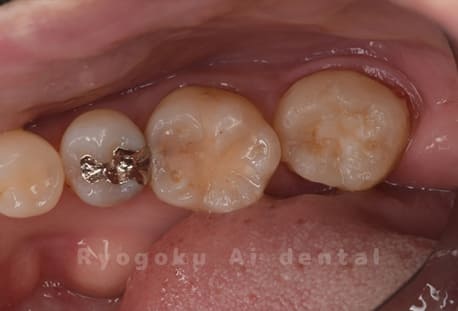

他院で右下の根の治療を行い、セラミックを被せる説明をされていたが、根の治療が終わらないため転院された患者さんです。隣の親知らずの抜歯の必要性と、根の治療を行なっている歯牙の予後が悪いため、移植治療を提案し、右下の親知らずの抜歯と同時に、右下の奥歯(7番)への移植治療を行いました。被せ物を行う必要もなく、順調に経過してます。